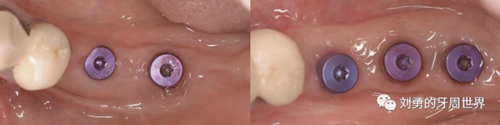

比如strip技術(shù),如下圖:

上圖中,種植體唇側(cè)缺乏附著齦,從上腭取瓣,常規(guī)做法:取長(zhǎng)而寬的齦瓣,這樣供區(qū)面積大,術(shù)后疼痛重。

為了減少痛感,從雙側(cè)上腭取多條長(zhǎng)而窄的齦瓣進(jìn)行移植,這樣每個(gè)供區(qū)的傷口都比較窄,可以減少術(shù)后的痛感。